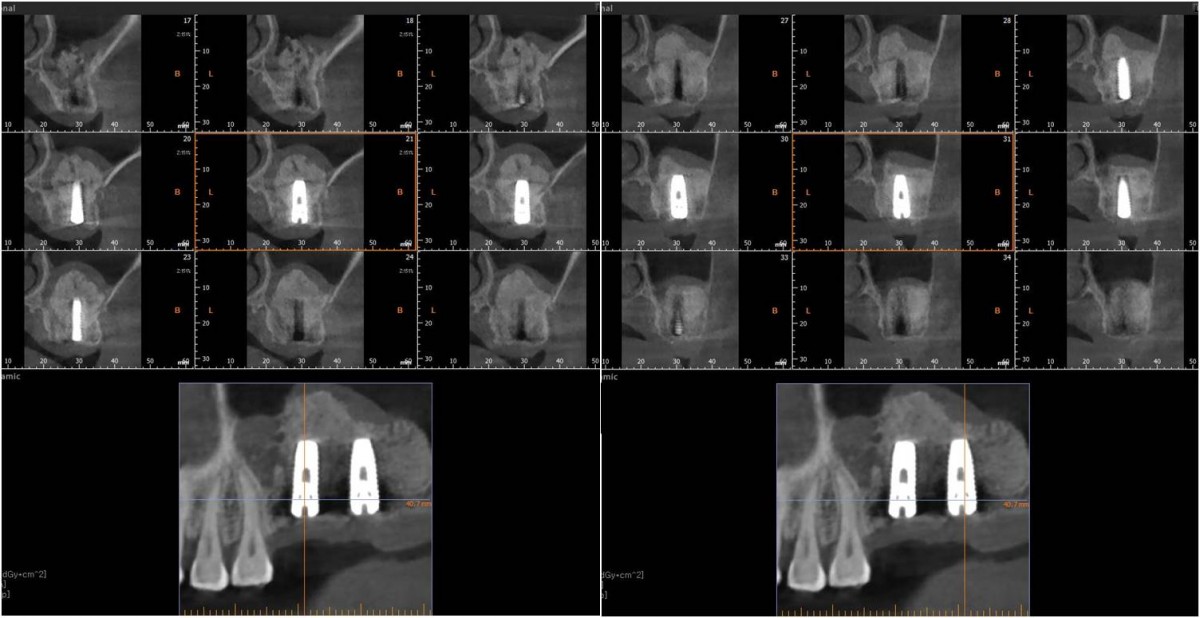

▲post-op panoramic radiograph.

▲. Panoramic radiograph after implant placement in the maxilla.(3 weeks after implant placement in the mandible)